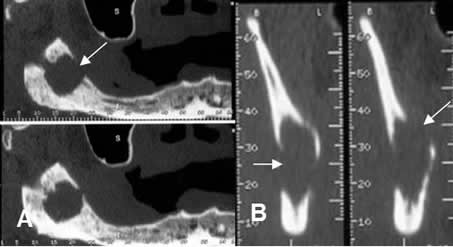

Fig 71. Tumor.

A: Panorámica de dentascan y B: TAC reconstrucción transversal. Imagen lítica, de bordes mal definidos y con ruptura de la cortical interna y externa, sobre el ángulo de la mandíbula, por tumor escamocelular.